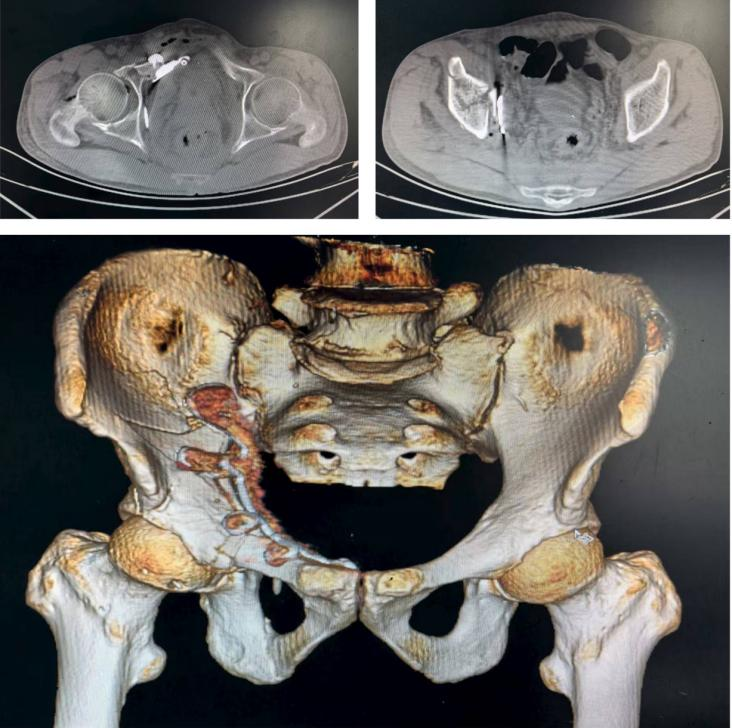

术前CT三维重建

术前三维重建和模拟手术